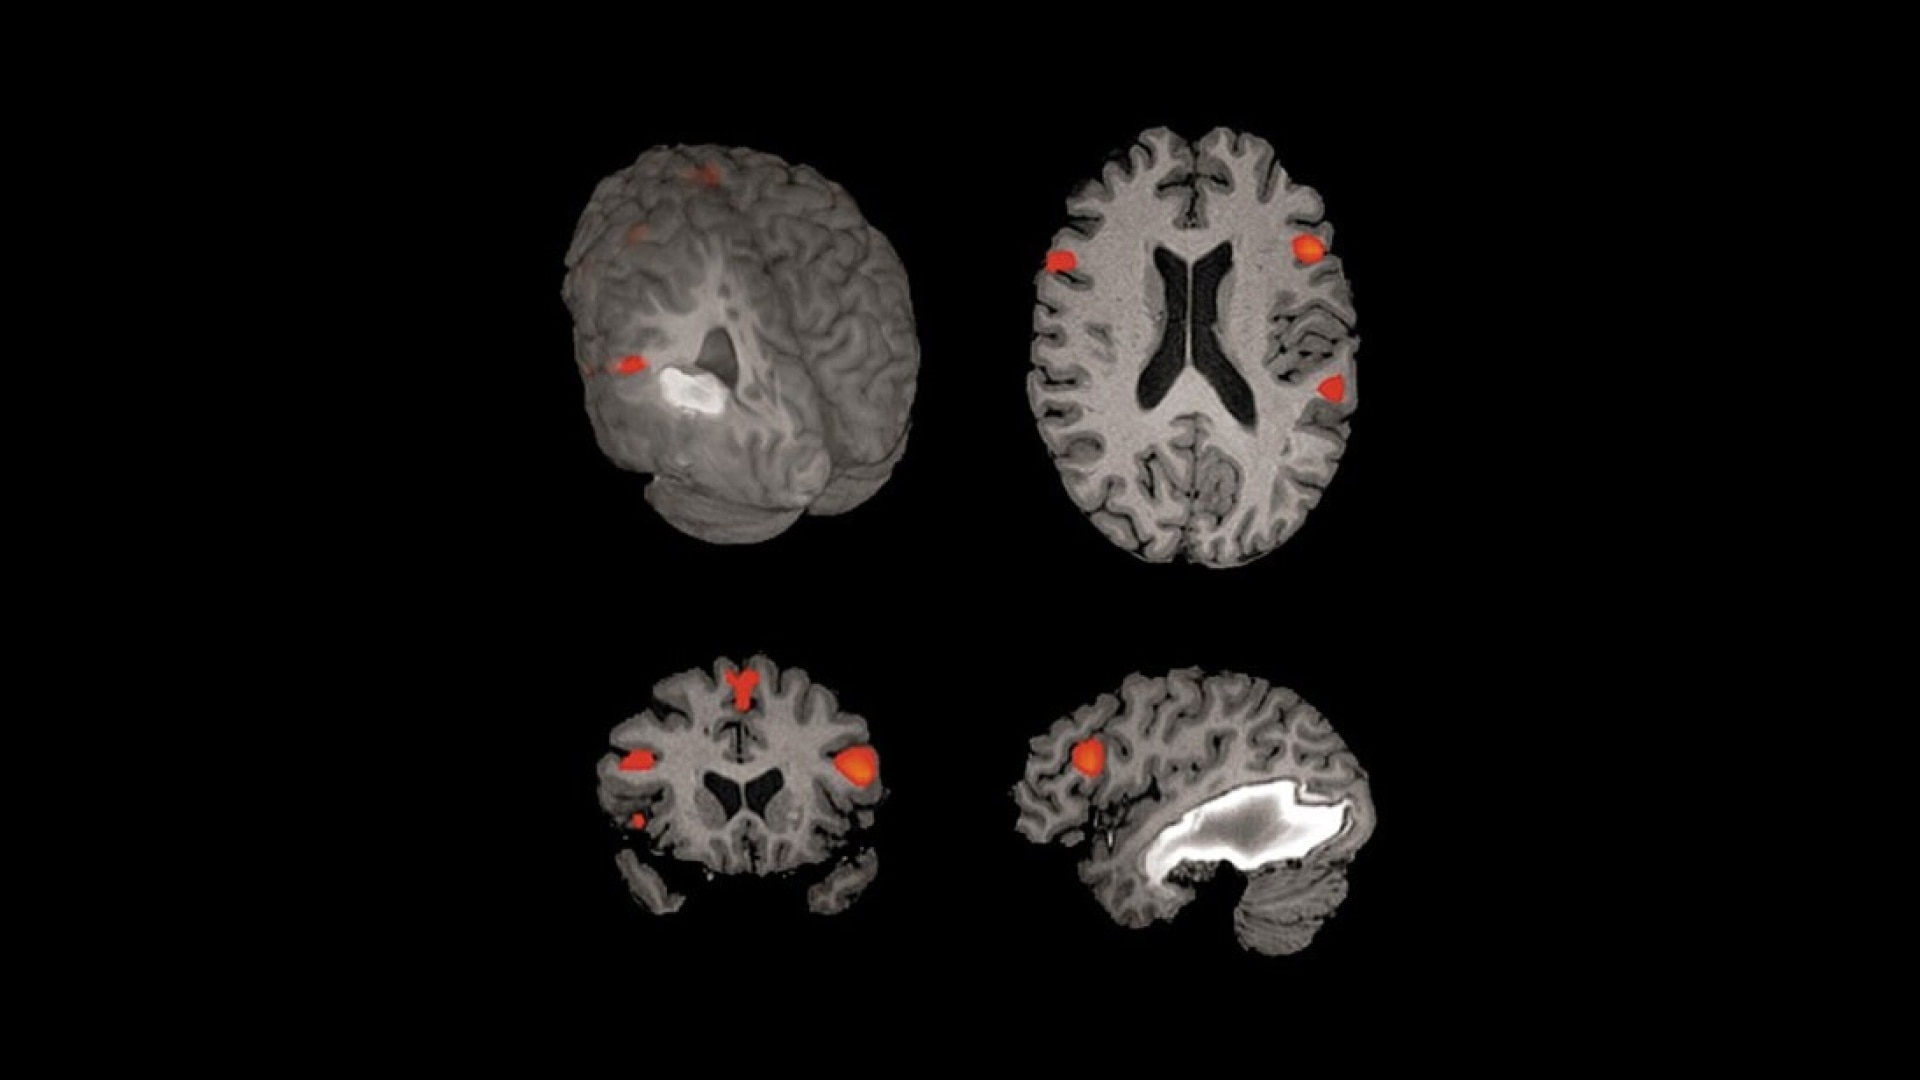

- Sophisticated visualization techniques that fuse analysis results with anatomical data

- Clear visualization with color activation maps and interactive thresholding

- Ability to transfer activations into high resolution 3D DICOM data sets for neurological applications